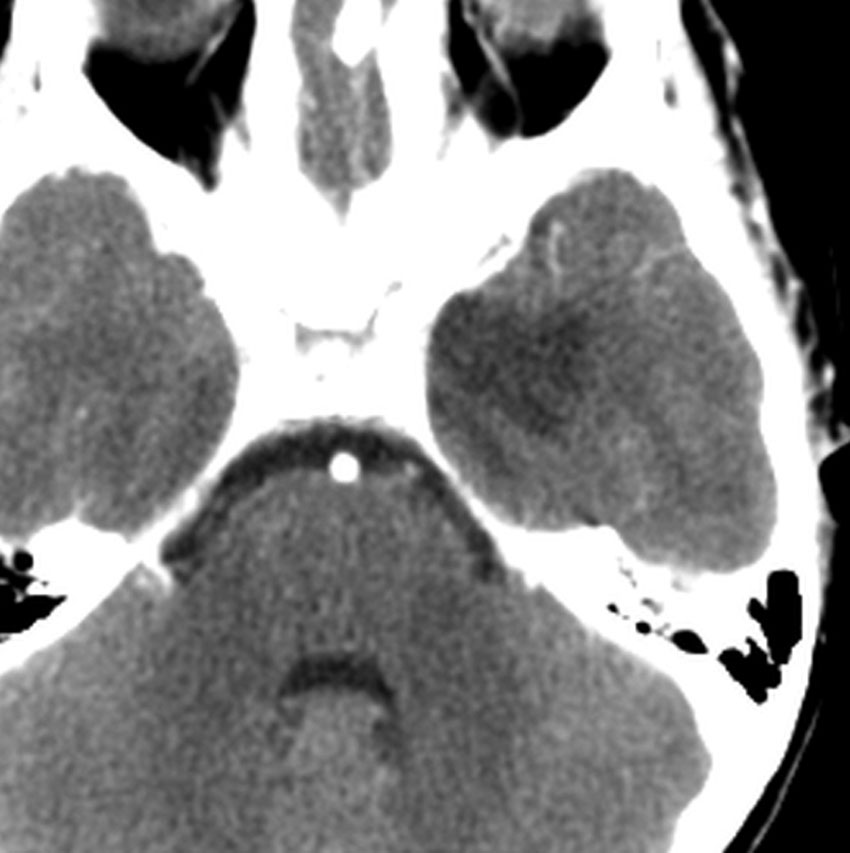

35歳,側頭葉てんかんで発症した右側頭葉の乏突起膠腫 グレード2です。全摘出して化学療法4コースと54グレイの局所放射線治療 generous local fieldを行いました。7年後に同じ部位に再発して摘出したところ退形成性乏突起膠腫 グレード3となっていました。手術摘出して,テモゾロマイド化学療法で維持療法をしていました。

その2年後の画像です。右小脳半球に再発しています。右側頭葉腫瘍との連続性は全くありませんでした。脳幹部にも腫瘍はありません。遠隔再発 remote recurrenceというもので,星細胞系腫瘍 astroytic tumor AAやGBMではよく知られている現象です。乏突起膠細胞系腫瘍でもまれにみられます。